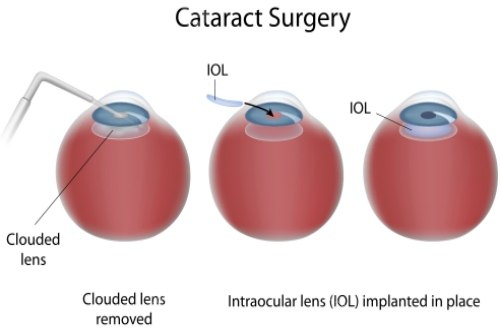

医疗服务不仅包括手术本身,还涵盖术前评估、术中操作与术后随访三个环节。术前评估会详细告知患者手术方案、潜在风险与术后注意事项,确保患者知情权;术中由专科医师团队操作,遵循标准化的诊疗规范;术后随访则是确保改善成效的关键,免费随访周期通常为术后1个月内,期间医生会监测视力修养情况,及时调整护理方案。